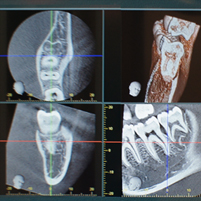

池尻シティ歯科は、歯科用CTを導入しています。この装置は、患部を従来の平面(二次元)画像ではなく立体(三次元)的に撮影できるものです。こうした最新の技術を活用し、より正確な診断を行い、適切な治療計画を立案することができます。